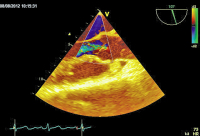

Parasternaler Längsschnitt

Abbildung 1: Parasternaler Längsschnitt: Die Aortenklappe weist zarte Klappentaschen mit einer unbehinderten Öffnungsfunktion auf.